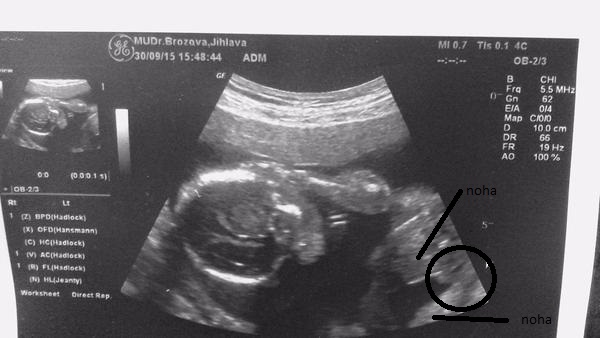

No prave něco tam visí ale co to je ze.Jinac foto je foceno tak ze dole je zadeček a nahoru vedou nozky

@satynka Mně je pohlaví jedno 🙂. No ale jak jsem doma koukala na tu fotku, tak se mi taky zdá že to je kluk. Leda že by to byl kousek bříška, ale to se mi nezdá tak symetrické ( vyznačím to )...

Tak ještě jak to vidím já 🙂, třeba to i pomůže někomu se lépe orientovat ve vlastních fotkách 😉